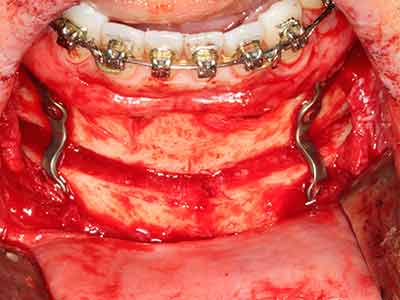

Sollen chirurgische Eingriffe mit unmittelbarer Knochenbeziehung an empfindlichen Strukturen wie Blutgefäßen oder Nerven erfolgen, so bergen rotierende Instrumente ein erhebliches Potential an iatrogener Schädigung. Gerade bei Nervdarstellungen nach iatrogener Schädigung, oder aber im Zuge einer Nervlateralisation für resektive und rekonstruktive Eingriffe oder Implantatinsertionen können piezoelektronische Geräte hilfreich sein Knochendeckel zu präparieren und nervnahe Hartgewebsanteile zu entfernen (Abb. 17-20). Ein leichter Kontakt des Nervstrangs zur Piezospitze bleibt dabei in der Regel folgenlos – allerdings kann eine unvorsichtige Vorgehensweise mit sägeartigen Bewegungen bzw. Ansätzen bei noch vorhandener knöcherner Unterlage durchaus temporäre oder aber auch permanente Nervschädigungen verursachen. Das Risiko einer solchen Schädigung wird jedoch als wesentliche geringer eingeschätzt als unter Anwendung von Säge- oder Fräsinstrumenten (Pereira, Gealh et al. 2014).